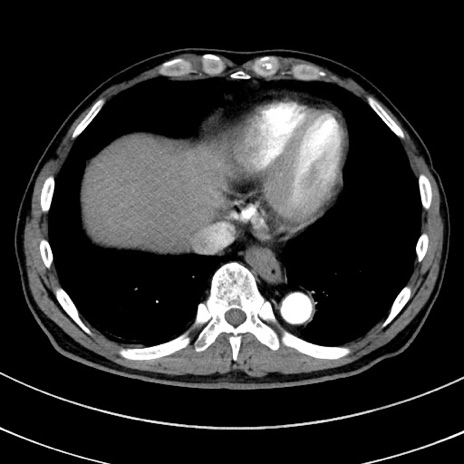

症例8(横断像)

【症例】 60歳代男性

【主訴】 黒色吐物

【現病歴】 4日前から嘔気自覚、2日前の朝食後にも嘔気あり、自分で手で嘔吐反射起こし嘔吐したところ血が混ざっていたため受診。

【既往歴】 5年前汎発性腹膜炎を伴う急性虫垂炎で手術、高血圧、前立腺肥大症、高脂血症

【身体所見】 腹部正中に手術癩痕あり 腹部平坦・軟圧痛なし膨満感あり

【データ】WBC 8400、CRP 4.54